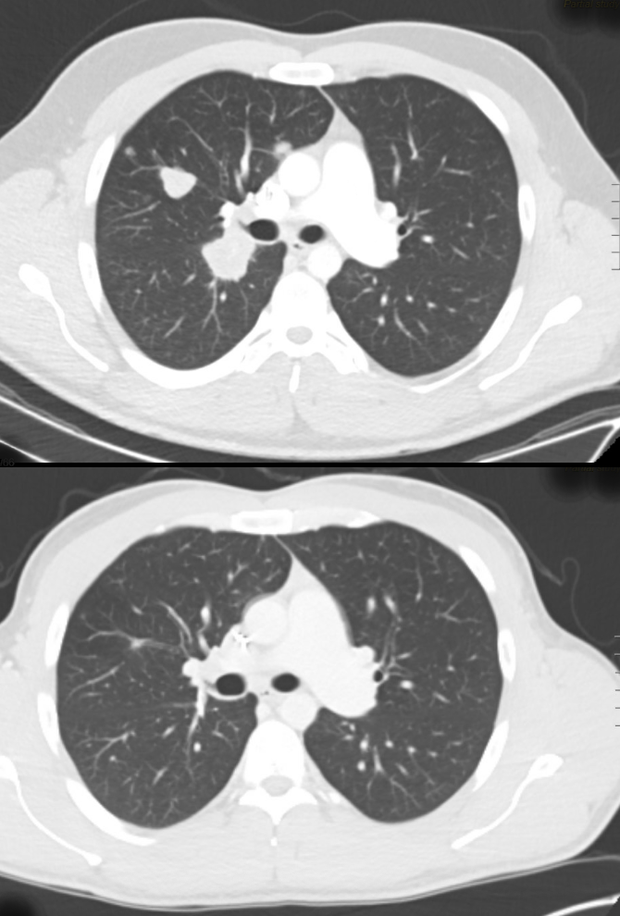

He was surprised by the suggestion. He felt fine. But a scan showed that Laird’s cancer had returned — and spread. There were 13 tumors in his lungs. One was the size of a golf ball. His doctor said Laird would likely have only about two years to live, even with treatment.

Scans showed Laird’s tumors “melting away,” DeVito said. He went from 13 tumors to three. The largest is just 0.6 millimeters — significantly smaller than the golfball-sized tumor that his doctor had first detected.